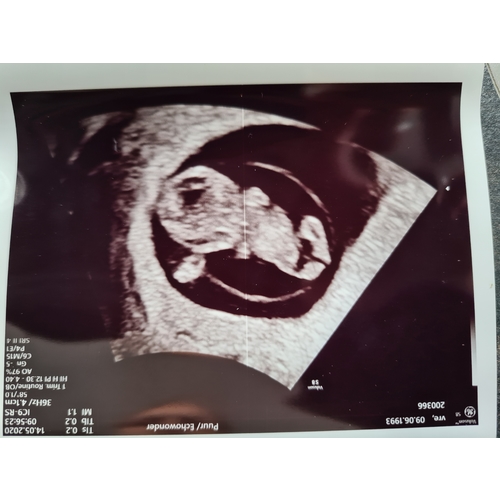

De kleine was bij 10.5 weken 6,4 cm

5,4 cm bedoelde ik

Met 10.3 weken was het, zover ik op de echo terug kon lezen, 3,6 cm. Baarmoeder was 15 of 16 cm denk ik dan.

Huh het is heel apart allemaal🙈 er komen verschillende lengtes bij verschillende duren. Ik had maandag de echo. Kleine was gemiddeld 4,8 cm en verloskundige zei dat ik dan uitkwam op 11+1 weken 😅🙈

Bij mij meette ze het op 8+1 op 16 mm.